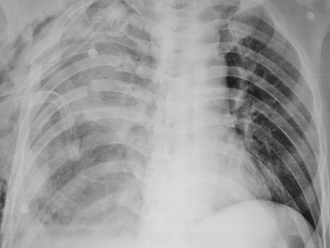

50歲男每年照肺部X光都正常 今年肺癌滿天星 醫嘆轉移了

肺癌多年是我國10大癌症死因首位,不少民眾為了身體健康,都會定期做肺部X光檢查。然而近日胸腔科醫師蘇一峰表示,有名50歲男子每年做X光檢查,去年報告還是正常的,不料今年一照「肺癌滿天星」,他忍不住嘆道,肺裡面都轉移了。

年輕工程師只是小咳 檢查驚肺部一異狀 醫:不寒而慄

肺癌是國人最好發的癌症,且有年輕化的趨勢。胸腔外科醫師謝義山分享有一位年輕竹科工程師,沒有吸菸,也沒有肺癌家族史,單純是因咳嗽好一陣子,因此自費做低劑量電腦斷層檢查,結果居然看到一顆1.3公分的毛玻璃結節,讓他不寒而慄,「年輕人得肺癌好像不是那麼罕見了。」

肺部結節出現1情況 癌變風險增13.77倍 尤其是女性

肺癌是國人最好發的癌症,越來越多人自費做低劑量電腦斷層檢查,但報告中,常出現肺結節、毛玻璃結節,讓民眾焦慮。對此,基因醫師張家銘表示,最新研究發現,女性較好發毛玻璃結節,而毛玻璃結節一旦出現實質成分,肺癌風險可高達原本的13.77倍,就像是一顆埋在肺裡的地雷,不能掉以輕心。

男頭皮冒詭異腫塊 一照肺部「滿天星」 醫嘆癌末了

肺癌是國人最好發的癌症,早期幾乎沒有症狀。胸腔內科醫師分享有位男子頭皮冒出腫塊,他不以為意,直到出現有點喘症狀,才被轉介到他的門診,經安排檢查,竟發現男子肺部已是「滿天星星」、佈滿腫瘤,確診是肺癌第4期,而頭皮腫塊其實是因癌細胞擴散,轉移過去的腫瘤。

小細胞肺癌難察覺 戒菸是上策

一名約60歲男性因突發性呼吸困難緊急送醫,到院時呼吸費力、窘迫,需額外氧氣治療才能維持正常血氧。經檢查,發現左肺有一顆壓迫肺動脈引發阻塞性肺炎的大型腫瘤,確診為小細胞肺癌。